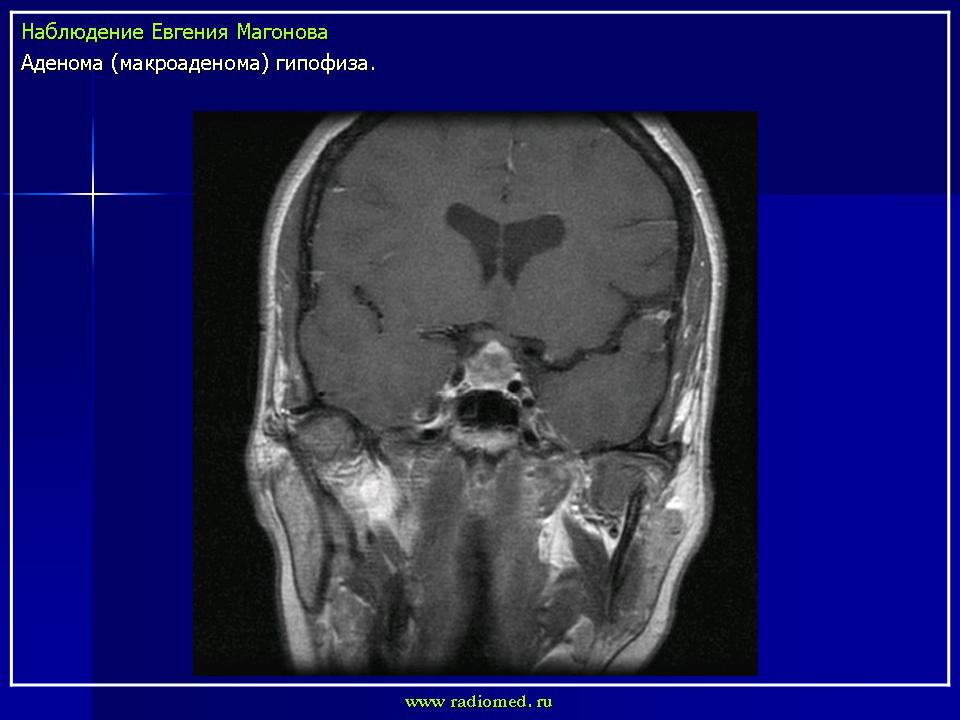

впервые настолько глубокие изменеия турецкого седла, что даже не требуется дообследование.

adenoma_gipofiza_1.jpg